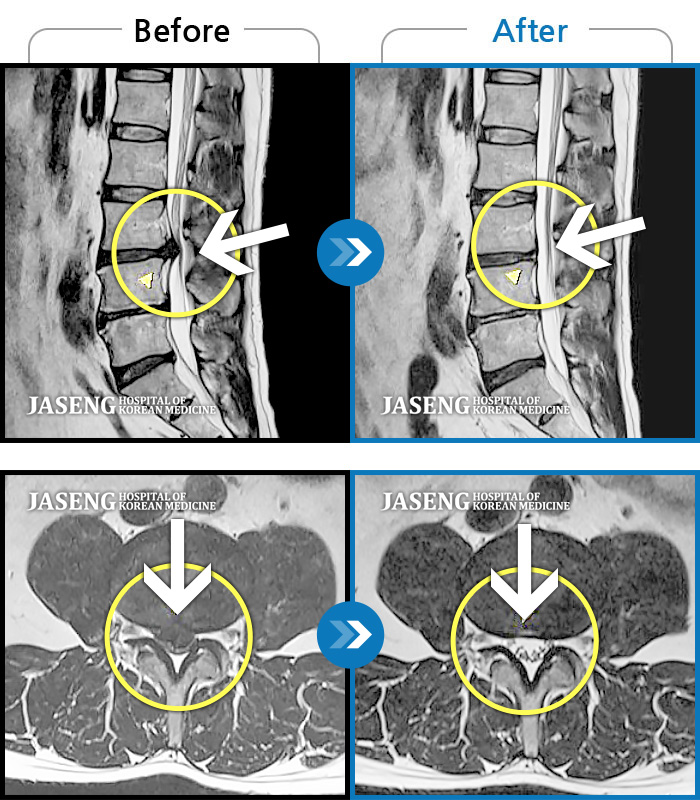

허리디스크

광주 · 김준수 원장

하부 요추, 골반 양측 통증, 좌측 다리 당김 및 통증

촬영시기

2017.10.06 ~ 2018.06.16

2018.06.22

조회수 10,212